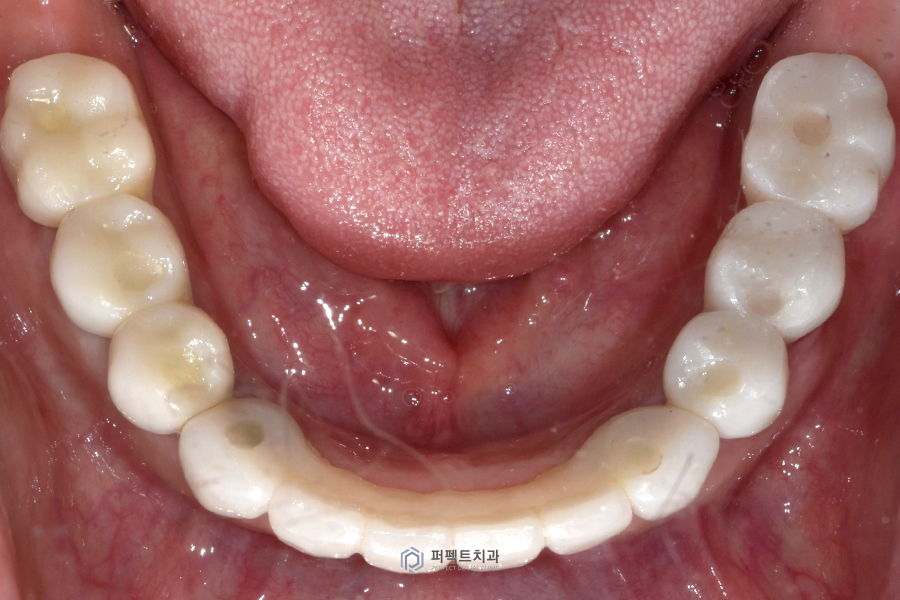

치료 후 구강사진

구강사진을 보시면 지르코니아 라는 재료를 이용해 전체를 수복했고, 교합도 깨끗하게 잘 물리도록 완성이 되었습니다.

치료 후(하악) 22.02.08~22.07.07

전 후 사진을 보시면 무너진 교합과 썩고 부러진 치아들을 수복한 케이스인 것을 보실 수 있습니다.

오늘은 전악 임플란트 케이스에 대해 알아보았는데요. 3개월에 걸쳐서 윗니 6개, 아랫니 8개를 심어서 전체 치아를 완성 해드리는 경우를 보여드렸고 보철물까지 지르코니아로 깨끗하게 마무리 된 전체 임플란트 케이스에 대해 같이 살펴보았습니다.